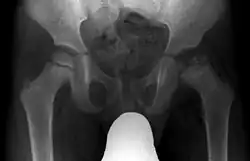

| Radiograph of a person with Legg–Calvé–Perthes disease | |

| Diagnostic method | X-Ray |

X-rays of the hip may suggest and/or verify the diagnosis. X-rays usually demonstrate a flattened, and later fragmented, femoral head. A bone scan or MRI may be useful in making the diagnosis in those cases where X-rays are inconclusive. Usually, plain radiographic changes are delayed six weeks or more from clinical onset, so bone scintigraphy and MRI are done for early diagnosis. MRI results are more accurate, i.e. 97–99% against 88–93% in plain radiography. If MRI or bone scans are necessary, a positive diagnosis relies upon patchy areas of vascularity to the capital femoral epiphysis (the developing femoral head).[11]